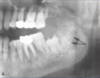

What is this radiographical finding?

Metastatic Carcinoma to Jaw Bones

C. Periapical image of a metastatic lesion of breast carcinoma; note the irregular widening of the periodontal membrane spaces and patchy sclerotic bone reaction, especially around the roots of the molars